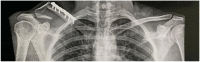

Case presentation: A 25-year-old male with previously (six years earlier) surgically treated clavicle fracture presented with a peri-implant clavicle fracture requiring surgical treatment. The management involved overlaying an implant to fix the lateral clavicle fracture without removing the previous plate. Complete bone healing was observed without any further complication.

Clinical discussion: Despite the low rate of implant failure in clavicle fractures, this complication occurs mainly in elderly patients with poor bone quality. No PIF have been described in the literature prior to this. This case report demonstrates a young patient with good bone quality and previous fracture fixation presenting with PIF which has now shown complete bone healing.

Conclusion: In this case, overlying an additional plate on the lateral clavicle portion without removing the previous plate increased the stability of the fracture. It demonstrates the value of overlaying plate osteosyntheses for patients with clavicle PIF.